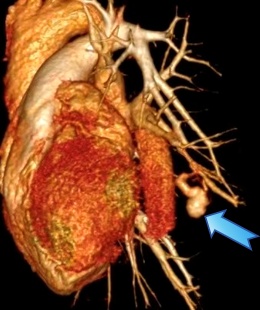

王女士术前CTA图像

王女士很快入住瑞金医院放射介入科病房。经过肺动脉CTA检查后,答案清晰——经团队讨论判定,该病变并非典型“肺内肿块”,而是位于左肺下叶分支血管内的肺动脉动脉瘤。该病变很少见,与咯血高度相关,一旦破裂可导致大出血,性命攸关。